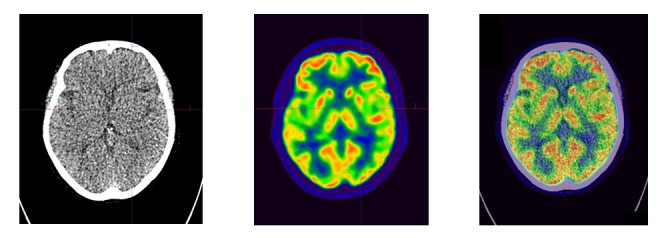

Case study of dementia: